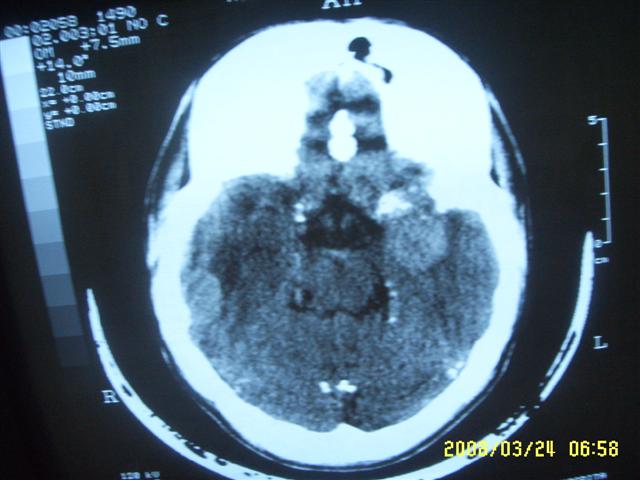

以下是引用dyqct在2008-4-2 20:09:00的发言:[br]考虑为:神经纤维瘤病(nf1型)。建议增强进一步检查。